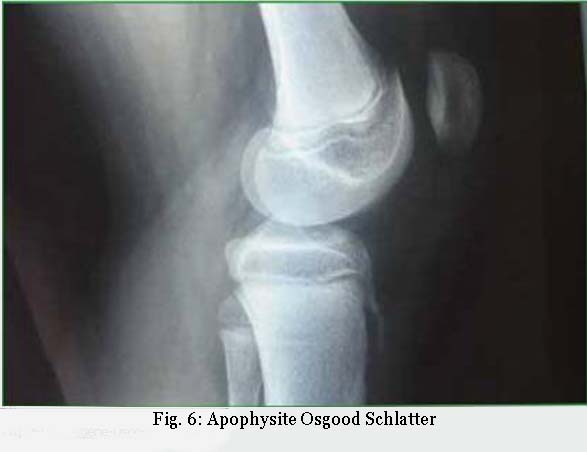

- apophysites du pré-adolescent et l’adolescent (maladie de Sever Osgood-Schlatter), avec des situations moins classiques telles le sourcil cotyloïdien ou l’épine iliaque antérieure;

Certaines douleurs de croissance sont très handicapantes, elles sont parfois confondues avec des douleurs articulaires. Ces enfants viennent en consultation au CETD avec un ou plusieurs examens radiologiques se limitant au seul espace articulaire (scanner et/ou IRM). Un jeu de radiographies face et profil du segment de membre aurait permis de faire le diagnostic d’apophysite. Une fois toutes les autres causes éliminées, le traitement est simple : arrêt de l’activité sportive en charge avec des étirements quotidiens fréquents (20 minutes journalières).

Les premiers étirements sont réalisés passivement par l’ostéopathe puis exécutés par l’enfant, mais l’arrêt du sport en charge est souvent mal vécu (fig. 6).